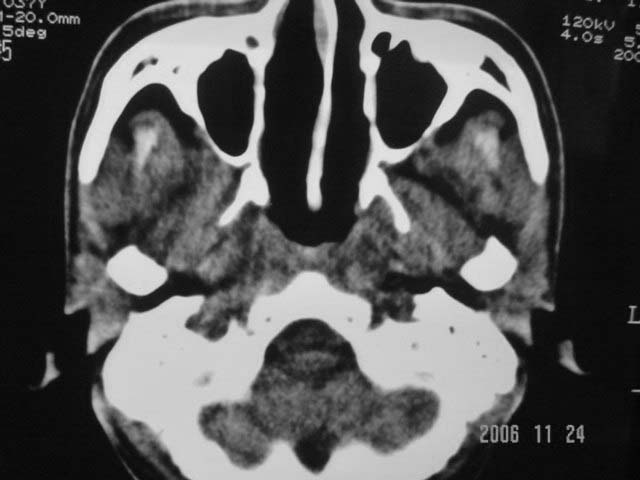

右侧鼻咽部软组织肿块,颅底骨质破坏,右侧颈部淋巴结肿大;诊断:鼻咽ca、右颈部淋巴结转移、颅底侵犯

右侧鼻口咽侧后壁不规则增厚,内可见密度不均匀性椭圆形软组织块影,边界欠清,咽旁间隙尚清.右颈部可见圆形软组织块影,鼻塞、耳鸣3个月,涕中带血2周,颈部可触及肿大淋巴结,考虑鼻咽癌,颈部淋巴转移.

右侧鼻咽后壁不规则增厚,内可见密度不均匀性椭圆形软组织块影,边界欠清,咽旁间隙尚清.右侧下方可见圆形软组织块影,双侧蝶窦呈均一高密度。

考虑:1、右侧鼻咽癌伴颈部淋巴结转移;

2、双侧蝶窦炎。

右侧鼻咽部软组织肿块,颅底骨质破坏,右侧颈部淋巴结肿大;诊断:右侧鼻咽ca伴右颈部淋巴结转移、颅底侵犯.

典型右侧鼻咽ca伴颈部淋巴结转移,中颅底骨侵蚀。

右侧鼻咽侧后壁不规则增厚,咽隐窝变钝,咽旁间隙变狭窄,见组织结节影[哨兵征],蝶骨似破坏,蝶窦内充塞软组织影,翼内外肌上分间隙模糊,右颈后三角区淋巴结肿大,右侧乳突增高气房消失。考虑鼻咽癌伴蝶窦侵犯及淋巴结转移,右侧浆液性中耳炎。其他恶性病变待排。